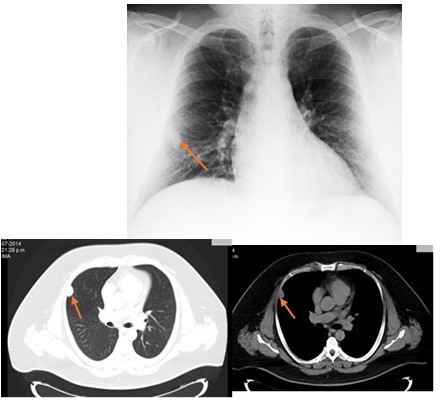

Paciente masculino de 41 años de edad, sin antecedentes médicos de importancia, quien consulta a la unidad de neumonologia por presentar procesos respiratorios de vías bajas en los últimos meses caracterizado por tos no productiva acompañada de dolor torácico, motivo por el cual se le indica radiografia de torax en donde se descubrió una imagen tipo nodular periférica en el 1/3 medio del pulmón derecho, de 1 cm de diámetro aproximadamente, sin calcificaciones en su interior y bien delimitado (Figura 1). Motivo por el cual se solicita tomografia computada torácica, donde con tomógrafo Multidetector VCTXT64® se confirmó la lesión nodular localizada a nivel de segmento lateral de lóbulo pulmonar medio que mide aproximadamente 11 mm x11 mm x 20 mm con un coeficiente 32 UH, de contornos bien definido sin calcificaciones en su interior resto del estudio sin alteración, conclusión: nódulo pulmonar (Figura 2). La exploración física era normal, asi como las pruebas analíticas elemental de sangre, orina, serología para el virus de la deficiencia humana, la exploración funcional respiratoria presentaba valores dentro de la normalidad. La reacción de Mantoux fue negativa a las 72 h. El cultivo, la coloración de Zielh-Nilzzen y el cultivo de esputo fueron negativos. Por lo cual es referido al servicio de cirugía de tórax para su evaluación y decisión de conducta terapéutica; el examen físico practicado se encontró dentro de límites normales, en vista de los hallazgo radiológicos y el examen físico la cual indicaba la presencia de patología inflamatoria, se decide dar conducta expectante con seguimiento con controles radiológicos, 14 meses después de la radiografia inicial, se aprecia aumento de dicha lesión con un diámetro de 3 cm aproximadamente (Figura 3), se realiza estudio tomografico multicorte 64 se confirma imagen de patrón nodular localizada a nivel de segmento lateral de lóbulo pulmonar medio que mide 2,5 cm x 1,8 cm de diámetro anteroposterior y transversal con un coeficiente de 27 UH, con presución diagnostica de nódulo subpleural en relación con mesotelomia (Figura 4).